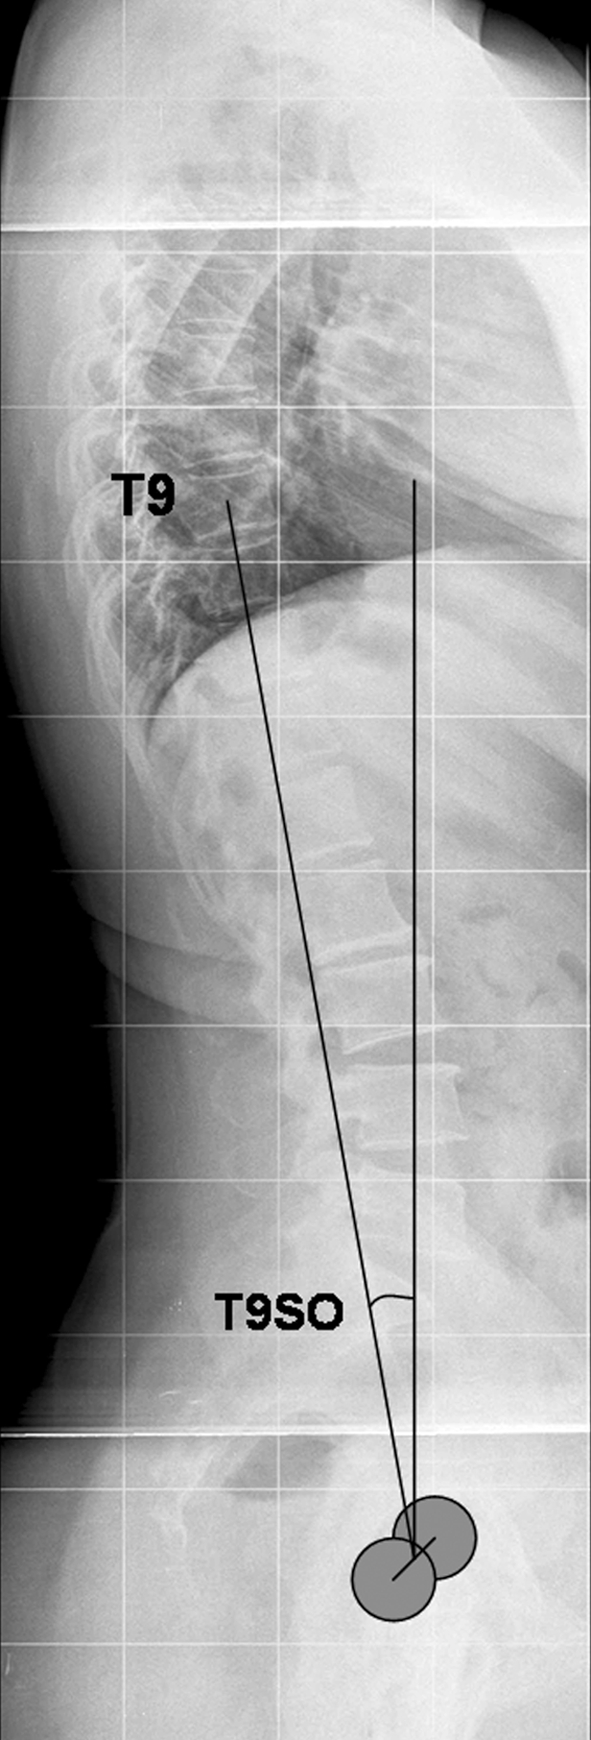

On lateral radiographs, overall sagittal balance was appreciated by measuring the T9 sagittal offset, i.e., the angle between a vertical line and the line between the center of the vertebral body of T9 and the center of the bicoxofemoral axis (Fig. 4). The values of T9 sagittal offset are negative when the angle opens on the posterior side of the T9 plumbline [36]. Thoracic kyphosis was measured from the upper endplate of T5 to the lower endplate of T12, and the lumbar lordosis was measured from the lower endplate of T12 to the upper endplate of S1.

Fig. 4.

T9 sagittal offset